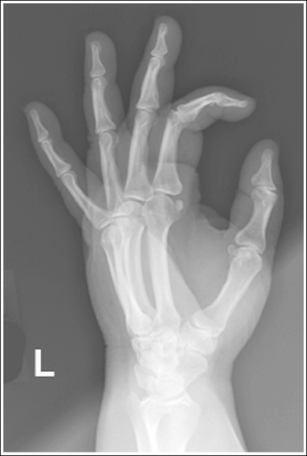

See Figure 4-24 and Box 4-9.

The hand has been externally rotated 45 degrees. Each of the second through fifth metacarpal midshafts demonstrate more concavity on one side than on the other and have varying amounts of space between them. The first and second metacarpal heads are not superimposed, the third through fifth metacarpal heads are slightly superimposed, and a slight space is present between the fourth and fifth metacarpal midshafts.

• To accomplish a PA oblique hand projection, begin with the hand in a PA projection. Then, externally rotate the hand until it forms a 45-degree angle with the IR (Figure 4-25). To confirm the 45-degree angle, it is best to view the hand and not the wrist. The wrist will demonstrate more than 45 degrees of obliquity when the hand is in a 45-degree oblique projection, so using the wrist can result in a miscalculation of the amount of obliquity. This is especially true if the humerus and forearm have not been placed on the same horizontal plane. When the patient has been positioned with the arm on the same horizontal plane, the ulnar styloid is demonstrated in profile medially on the image. A radiolucent immobilization device can be used to help maintain this position.

• Verifying PA oblique hand projection. A 45-degree PA oblique hand projection can be recognized by the amount of metacarpal midshaft and metacarpal head superimposition. If the hand has not been rotated enough, the metacarpal relationship is similar to that demonstrated on a PA projection of the hand: The midshafts of the metacarpals are almost evenly spaced, and the metacarpal heads are not superimposed (see Image 22). On a 45-degree PA oblique hand projection, a space should be maintained between the fourth and fifth metacarpal midshafts. If the hand is rotated more than 45 degrees, this space is obscured and the fourth and fifth metacarpals demonstrate some degree of superimposition (see Image 23).

Image 22

Image 23

No soft tissue overlap of adjacent digits is present.

• Fingers should be spread slightly to prevent soft tissue overlapping (Images 24 and 25).

Image 24

Image 25

The IP and MP joints are visible as open spaces, and the phalanges are demonstrated without foreshortening. The thumb's position may vary from a lateral to a PA oblique projection.

• The IP and MP joint spaces are open and the phalanges are not foreshortened when the hand and fingers are fully extended and aligned parallel with the IR. An immobilization device should be used to help the patient maintain this positioning.

• Disadvantages of using fingers as prop. A common positioning error in PA oblique hand projection is to use the patient's fingers instead of an immobilization device to maintain the oblique position. For this positioning, the fingers are flexed until the fingertips touch the IR to prop the hand (Figure 4-26). Such positioning closes the IP joint spaces and foreshortens the phalanges (Images 23 and 25).

The third MP joint is at the center of the exposure field. The distal, middle, and proximal phalanges, the metacarpals, the carpals, and approximately 1 inch (2.5 cm) of the distal radius and ulna are included within the collimated field.

• Center a perpendicular central ray to the third MP joint to place it in the center of the collimated light field. The MP joint is situated just slightly distal to the head of the third metacarpal. Once the central ray is centered, open the longitudinal collimation to include the distal phalanges and the distal forearm. Transversely collimate to within 0.5 inch (1.25 cm) of the first and fifth finger's skin line.

• Either half of a 10- × 12-inch (24- × 30-cm) detailed screen-film IR placed crosswise or a single 8- ×10-inch (18- × 24-cm) digital IR placed lengthwise should be adequate to include all the required anatomic structures.

The metacarpal heads demonstrate only slight superimposition, the metacarpal midshaft concavities are fairly uniform, and the spaces between the metacarpal midshafts are almost equal. The hand was not rotated enough. Open collimation includes 1 inch of radius and ulna.

The midshafts of the third through fifth metacarpals are superimposed. The patient's hand was placed at more than 45 degrees of obliquity. The phalanges are foreshortened, and the IP joints spaces are closed. The fingers were not positioned parallel with the IR, but instead were used to prop the hand (see Figure 4-26).

Internally rotate the hand until the metacarpals and the IR form a 45-degree angle and extend the fingers, placing them parallel with the IR.

Soft tissue and bony structure overlap of the digits is present. The fingers were not spread apart.

The distal and middle phalanges are foreshortened, and the IP joint spaces are closed. The fingers were not positioned parallel with the IR, but were instead used to prop the hand (see Figure 4-26).